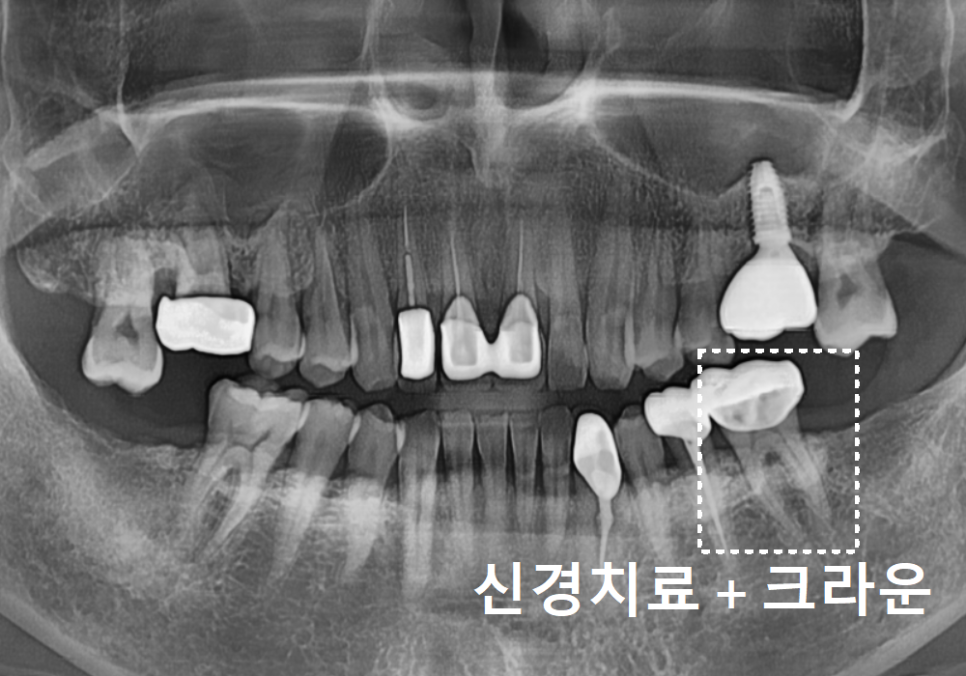

이번엔 반대쪽인

왼쪽 아래 어금니인 금니가

'툭' 하고 빠지신 건데요.

지난번 발치의 아픈 기억 때문인지,

"이번에도 뽑아야 하나요...?"

하며 걱정이 태산 같으신 모습이었습니다.

조심스럽게 빠진 자리를 살펴보니,

역시나 치아 내부에

까맣게 충치가 진행되어 있었죠.

엑스레이와 구강 상태를 꼼꼼히 확인해 보니,

이번 치아는 다행히

발치 없이 충분히 살려서 쓸 수 있는 상태였습니다.

240812

충치가 있긴 했지만

치아 뿌리는 튼튼했기에,

치아 내부의 오염된 신경관을

청소하는 신경치료를 진행했습니다.

251010

오염된 신경을 4번에 걸쳐

꼼꼼히 제거하고 소독한 뒤,

이번에는 구멍이 잘 나지 않는

단단한 재료인 '지르코니아'로 씌워,

튼튼하게 마무리해 드렸습니다.

251103